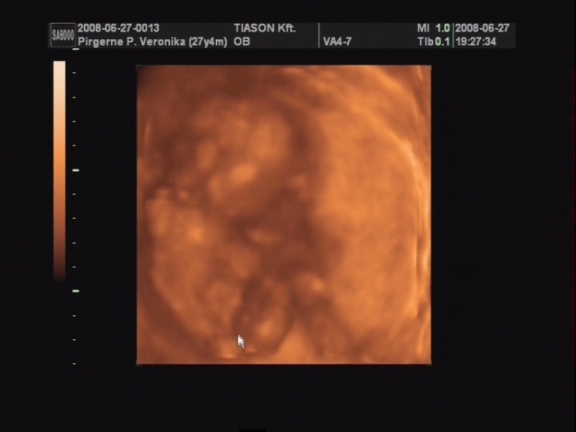

Csodálatos élmény volt az uh!

Nem lehetett még látni, kisfiú vagy kislány van odabent, de nagyon nagyon jó lett a videó. Rengeteget mozgott, rugdalózott, kitámasztotta magát, kalimpált a kezével, iszonyú jó volt. Még a pofijáról is van kép, az is egészen jól látszik.

Egyszóval nagy a boldogságunk, gondolhatjátok. :lol:

Próbálok majd egy két képet levarázsolni a videóról és felrakni hétvégén.